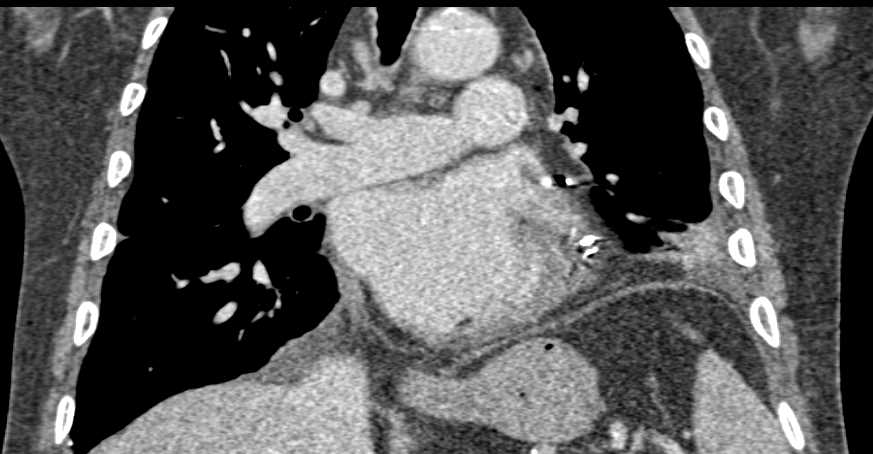

Post Cardiac Surgery Changes